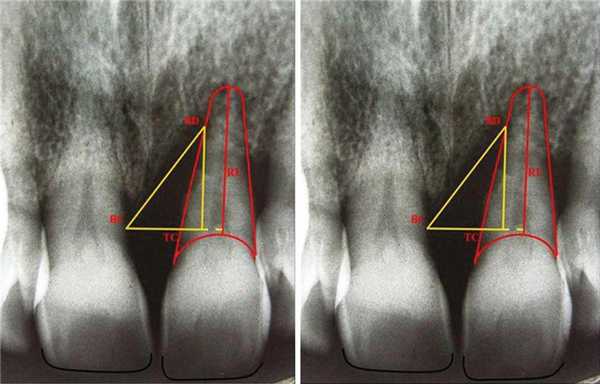

Также определена глубина пародонтального кармана в шести точках: дистолингвальной (DL), лингвальной (L), Мезиолингвальной (ML), Дистобуккальной (DB), Буккальной (B) и Мезиобуккальной (MB) при помощи зонда Уильяма в мм. Кроме того градуированным зондом измерена (в мм) высота от верхушки сосочка до режущего края для сравнения этого показателя у соседних зубов. Затем изготовлены прицельные рентгенограммы. Для достижения правильной позиции пленки изготовлен держатель из силикона для каждого пациента исходя из окклюзионной составляющей. Пленка располагалась параллельно длиной оси и перпендикулярно к источнику с дозировкой 40 Kvp. На рентгенограмме перпендикулярно к корню проведена линия (Tooth Crest point, TC) от самой высокой точки гребня кости (BC). Расстояние между TC и BC показывает ширину костный дефект (DW). Затем проведена линия от BC к точке наибольшего костного дефекта. Расстояние между TC и дефектом кости (BD) показывает глубину дефекта (DD). Для измерения длины корня (RL), проведена линия от нижней границы корня к нижней границе цементо-эмалевого соединения (Фото 2).

Фото 2: Наиболее верхняя граница костного гребня определена как точка BC. Точка, образующаяся при проведении перпендикулярной линии к корню от ВС определена как точка гребень-зуб (TC). Точка, образующаяся при проведении линии из ВС к наиболее глубокой зоне костного дефекта определена точкой BD. Измерение от нижней границы корня до нижней границы цементо-эмалевого соединения признано длиной корня.